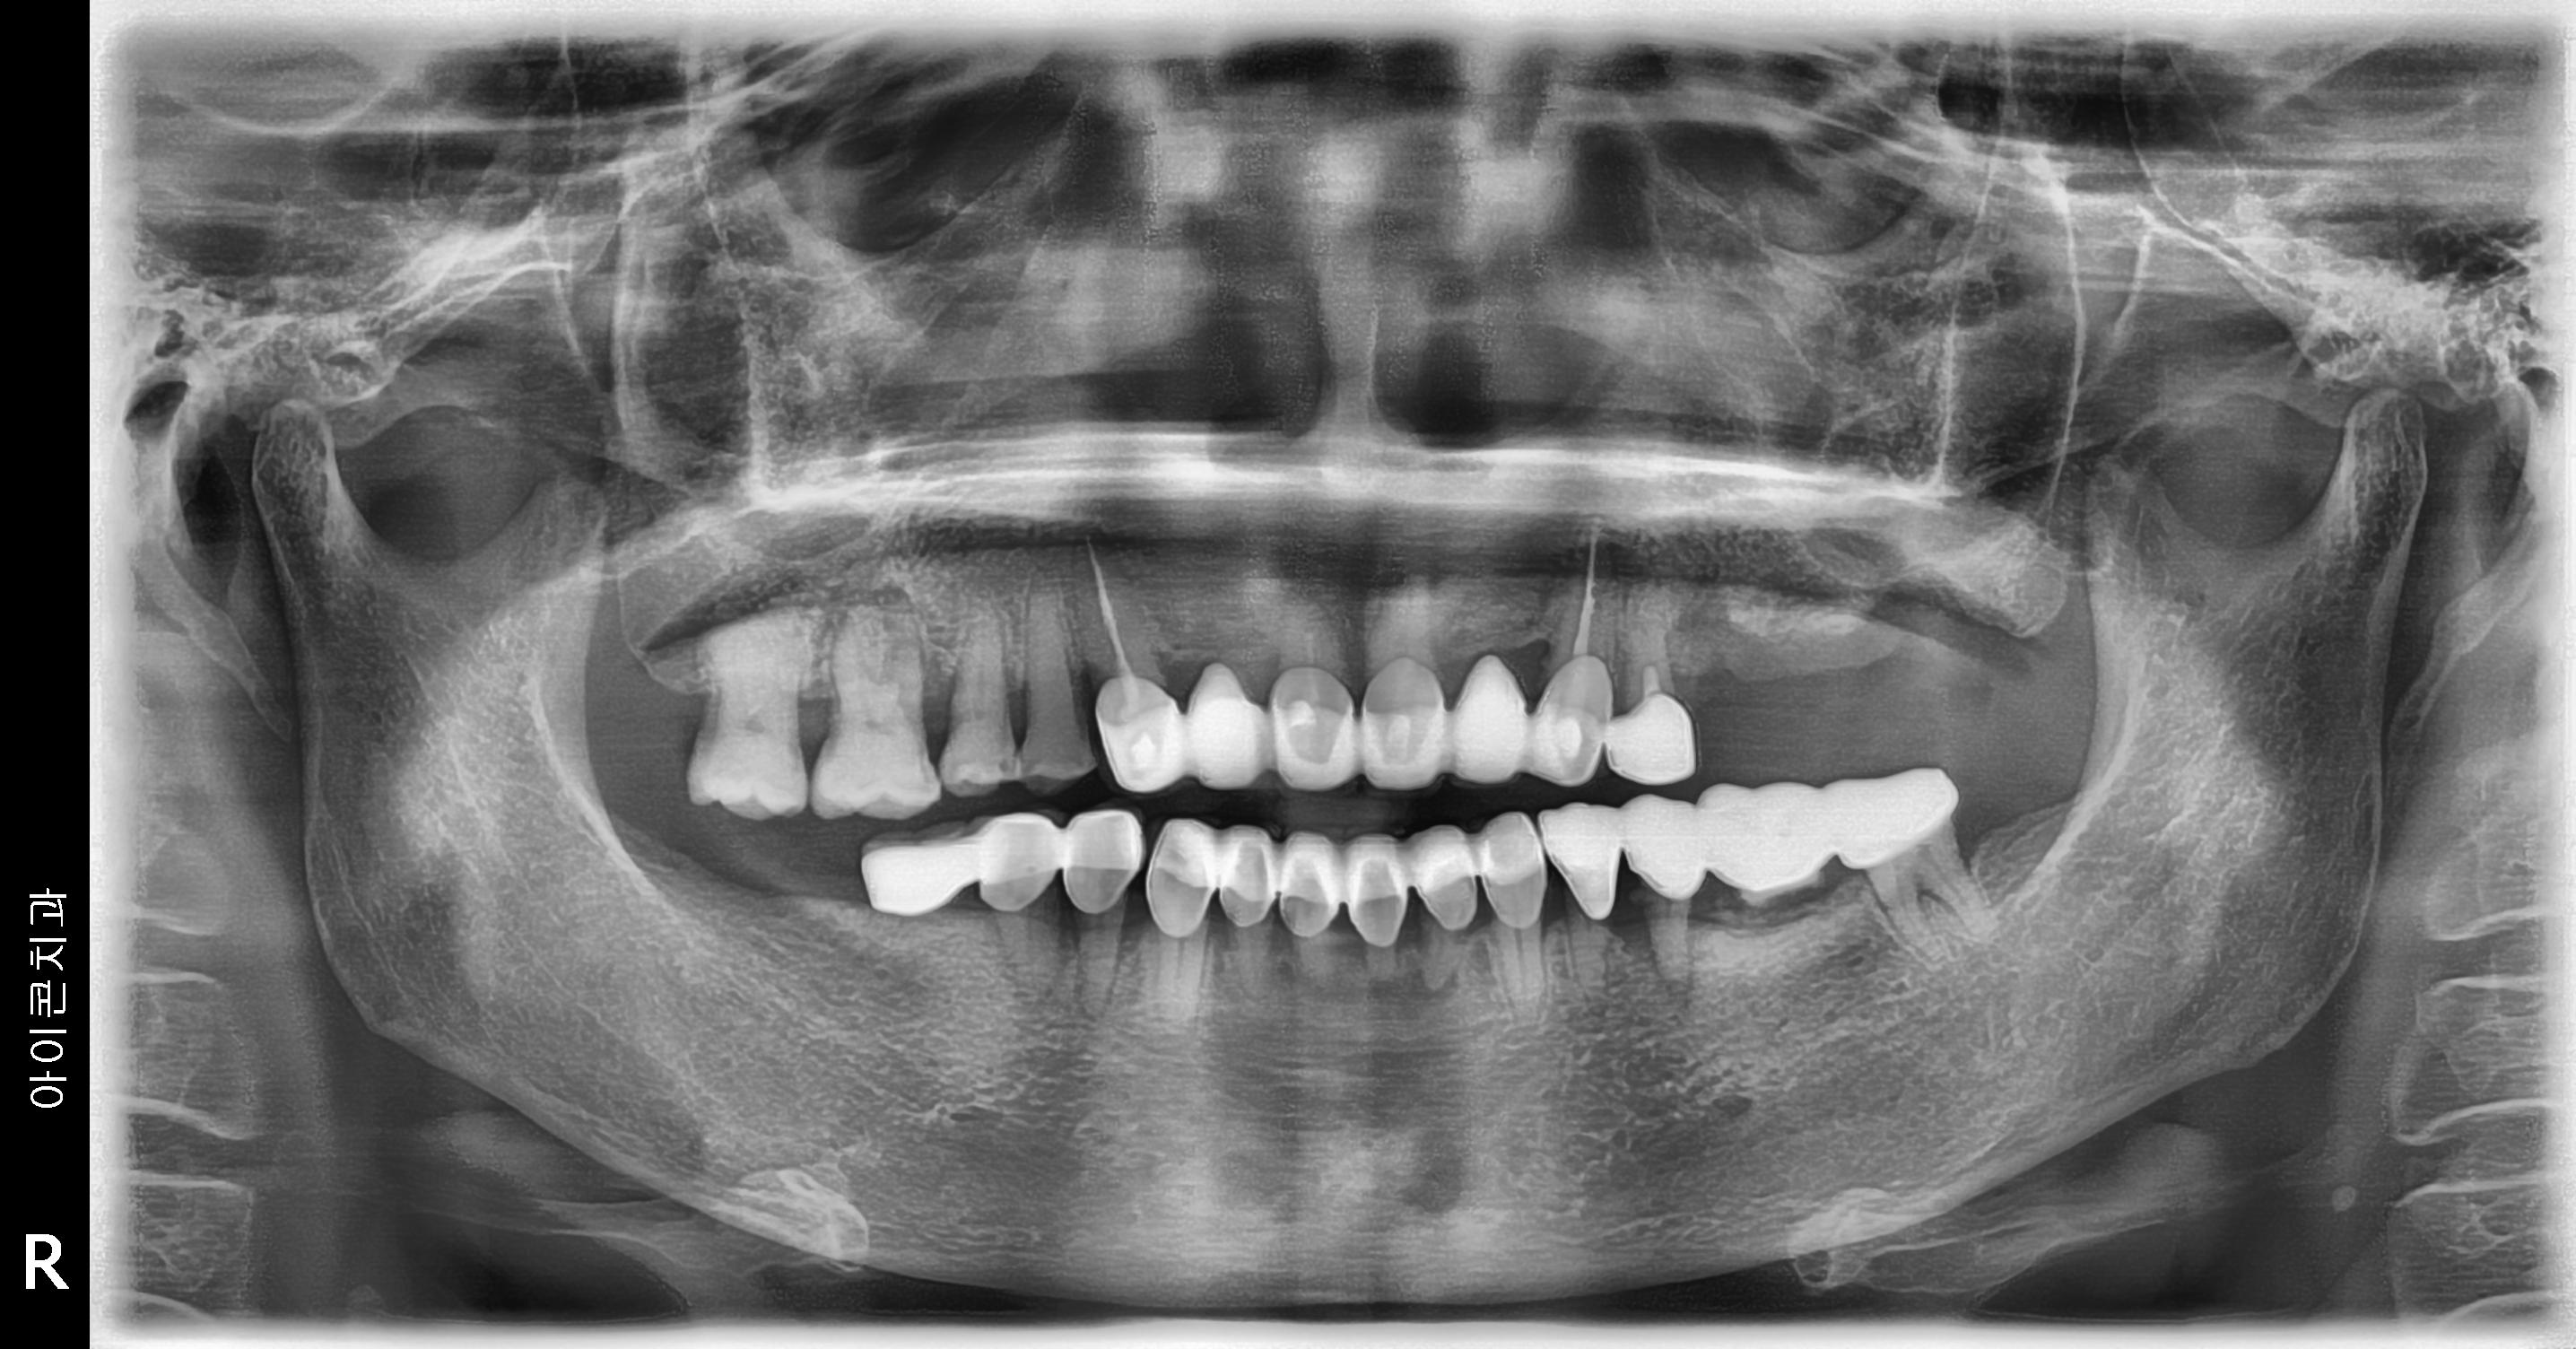

수술 전

수술 후

좌측 임플란트 흔들림 재수술 사례

전후사진